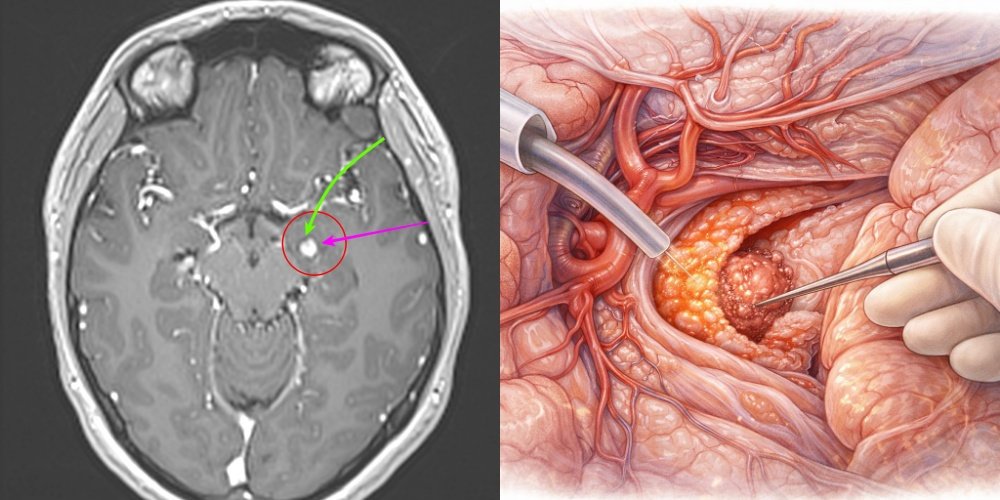

Pentru a ajunge la leziune existau două posibilități chirurgicale: o cale directă prin lobul temporal sau o cale mai complexă, prin fisura sylviană – un coridor natural al creierului.

Prima variantă ar fi presupus traversarea și sacrificarea unei porțiuni de țesut cerebral sănătos. A doua, deși mai laborioasă, oferea șansa de a ajunge la tumoră folosind spațiile naturale dintre structurile creierului.

Din acest motiv a fost ales abordul trans-sylvian, o tehnică microchirurgicală mai dificilă, dar mai delicată cu creierul.